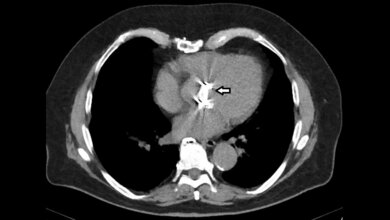

Für die Diagnostik sind sie unverzichtbar: Bildgebende Verfahren in der Medizin. Egal ob bei der Diagnose, Therapie oder Nachuntersuchung, in der Brustkrebsfrüherkennung beispielsweise dominiert die Mammografie mit Röntgenstrahlen. Sie liefert schnelle und präzise zweidimensionale Bilder. Bei der Krebsdiagnose kommt die dreidimensionale Computertomografie (CT) zum Einsatz. Diese kann aufgrund der hohen Röntgenstrahlenbelastung allerdings selbst zu einem Gesundheitsrisiko werden. Während die natürliche jährliche Strahlenexposition bei etwa 2,1 Millisievert liegt, beträgt die Strahlenbelastung eines Brustkorb-CTs etwa das Dreifache. Im Projekt „Multi-Med“, abgeleitet von Multimodale medizinische Bildgebung in 3D, entwickeln Fraunhofer-Forschende nun ein Verfahren, das Röntgen und Radar kombiniert. Es soll die Diagnose, Überwachung und Therapie von Brust- und Lungenkrebs nicht nur verbessern, sondern auch schonender gestalten.

Um die Bildqualität weiter zu verbessern und innen liegende Bereiche des Körpers mittels Radar dreidimensional darstellen zu können, arbeiten die Forschenden an neuen Radar-Rekonstruktionsalgorithmen. Sie sollen die Bildqualität erhöhen und die Gewebeeigenschaften besser erfassen. Gleichzeitig soll die Röntgen-CT-Rekonstruktion optimiert werden: Radardaten sollen in die Röntgenrekonstruktion einfließen, sodass ein multimodaler CT-Algorithmus entsteht. Das soll die Qualität und Detailgenauigkeit der CT-Bilder verbessern, störende Artefakte reduzieren und die Strahlenbelastung senken. Das Forscherteam hat bereits erste Messphantome entwickelt, um das Verfahren zu testen.